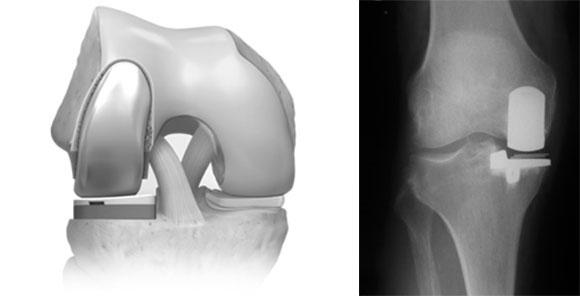

Одномыщелковое эндопротезирование

Предполагает замену элементов либо во внутренней, либо во внешней части сустава. Операция проводится при ограниченных повреждениях колена. Противопоказанием для одномыщелкового протезирования могут быть ожирение, повреждение связок или наличие определенных системных заболеваний.

Стоит подчеркнуть, что такой тип протезирования считается наименее травматичным, не требующим длительной реабилитации после вмешательства.

После процедуры эндопротезирования пациент восстанавливается в короткие сроки и может вернуться к полноценной жизни без каких-либо ограничений.